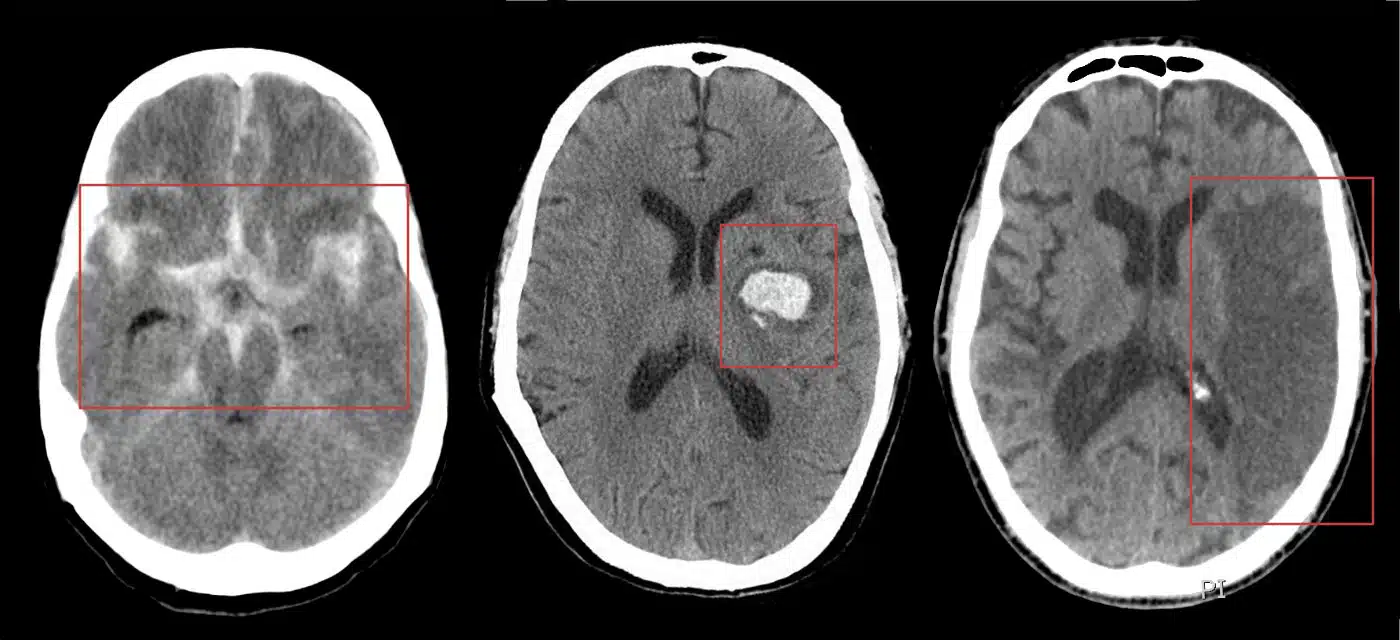

Acidente Vascular Cerebral (AVC)

Na fase aguda, a TC pode mostrar perda da diferenciação córtico-medular ou hiperdensidade arterial espontânea. Na fase subaguda, áreas hipodensas bem delimitadas.

Meningioma

Massa extra-axial com base de implantação em meninges, geralmente com realce homogêneo pelo contraste. Pode apresentar calcificações e hiperostose óssea adjacente.